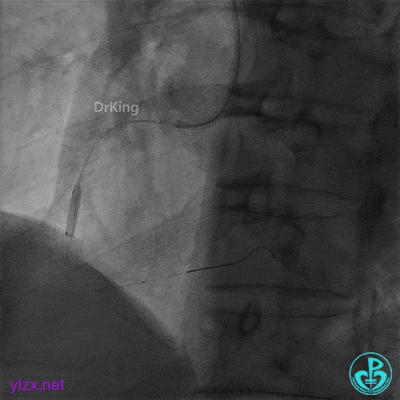

心脏叩击后恢复窦性心律,阿托品1mg静推,去甲肾上腺素静脉滴注,冠脉内推注尿激酶原20mg。

快速串联植入3.5×29mm、3.5×23mm支架。

并反复经刺破球囊冠脉内静推硝普钠5次(100μg/次),右冠脉血流恢复TIMI 3级,右冠脉近端可见夹层。

支架近端植入3.5×13mm支架覆盖夹层。